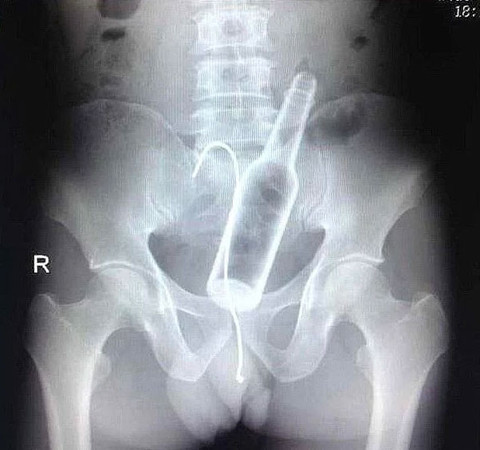

Röntgen filmlerinde karşılaşılan tuhaf cisimler

Galerinin tamamı için tıklayınızÇekilen röntgen filmlerinde bazı cisimlerin oraya nasıl

girdiğini merak etmemek elde değil.

Yanlışlıkla olduğunu ve şişeyi çıkarmaya çalışmadığını iddia etmiş

fakat röntgende şişeyi çıkarmaya çalıştığı kıvrılmış kablonun da

orada olduğu görülüyor.